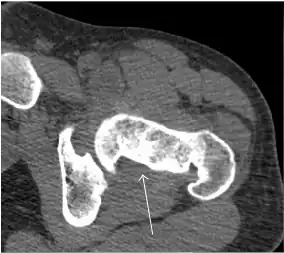

Synovial chondromatosis can be confidently diagnosed by X-ray when calcified cartilaginous chondromas are seen. However, other synovial proliferative processes, such as pigmented villonodular synovitis, require MRI for accurate diagnosis, although noncalcified synovitis can be suspected in radiographs by indirect signs, such as soft tissue swelling and/or erosions in the femoral head, femoral neck, or acetabulum (Figure 7).[1]

Figure 7:

-

Axial CT image of pigmented villonodular synovitis eroding the posterior cortex of the femoral neck.[1] -

Sagittal T2* gradient echo image showing a posterior soft tissue mass with hypointense areas secondary to hemosiderin deposition.[1] -

X-ray of synovial chondromatosis.[1] -

CT of synovial chondromatosis.[1]

In synovial proliferative disorders, MRI demonstrates synovial hypertrophy. In the case of PVNS, characteristic foci of low signal intensity related to hemosiderin deposition are better seen on gradient echo T2* images (Figure 7). In the case of synovial osteochondromatosis, the synovial hypertrophy is accompanied by intermediate signal cartilaginous loose bodies and/or low signal calcified loose bodies.[1]